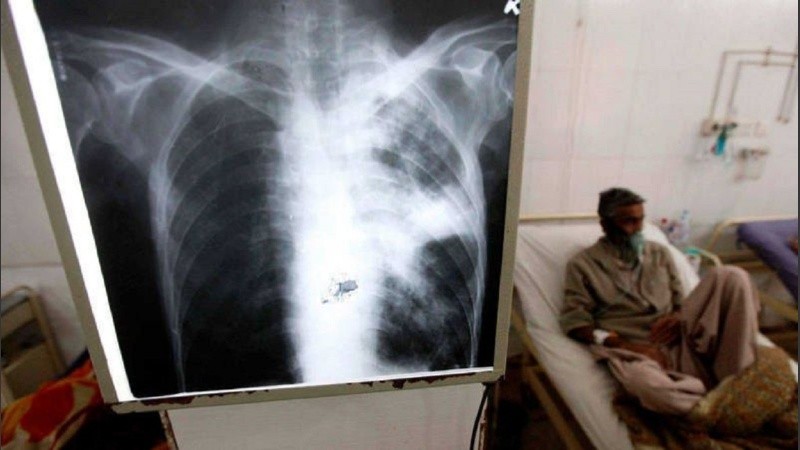

Según difundieron desde Aamr en su informe oficial, en Argentina la tuberculosis es un problema de salud pública que se agrava: “Solo en 2025 la notificación alcanzó un total de 16.445 casos (Boletín Epidemiológico Nacional Nro. 790/2025), lo que representa un aumento del 3,9% respecto a 2024 y un crecimiento del 79,7% desde 2020”.

Este crecimiento es, según la mirada especialista, “multifactorial y se vincula con el debilitamiento de programas de control, dificultades en el acceso al diagnóstico temprano, interrupciones en los tratamientos, desigualdades sociales persistentes y condiciones de vida que favorecen la transmisión como el hacinamiento y la vulnerabilidad socioeconómica”.

La Tasa Nacional de Tuberculosis trepó a 34,6 casos cada 100.000 habitantes, y las jurisdicciones con mayor carga son Jujuy, Salta, CABA, Buenos Aires, Chaco y Formosa.

Once provincias muestran un aumento significativo, entre ellas Santa Fe. Estas son Buenos Aires, CABA, Salta, Chaco, Córdoba, Jujuy, Tucumán, Entre Ríos, Corrientes y Tierra del Fuego.

Es preocupante el número creciente de casos en hombres jóvenes: el grupo de entre 15 y 44 años concentra el 60,7% del total. También hay un marcado incremento en casos en menores de 20 años, siendo el 16,6% del total.